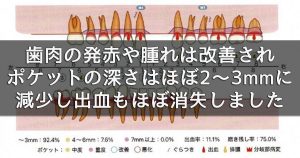

3週間後の再評価では、歯肉の発赤が明らかに改善し、腫れも引いてポケット深さは2~3 mmに改善。歯磨き時にも出血しなくなりました。

3週間後の再評価では、歯肉の発赤が明らかに改善し、腫れも引いてポケット深さは2~3 mmに改善。歯磨き時にも出血しなくなりました。